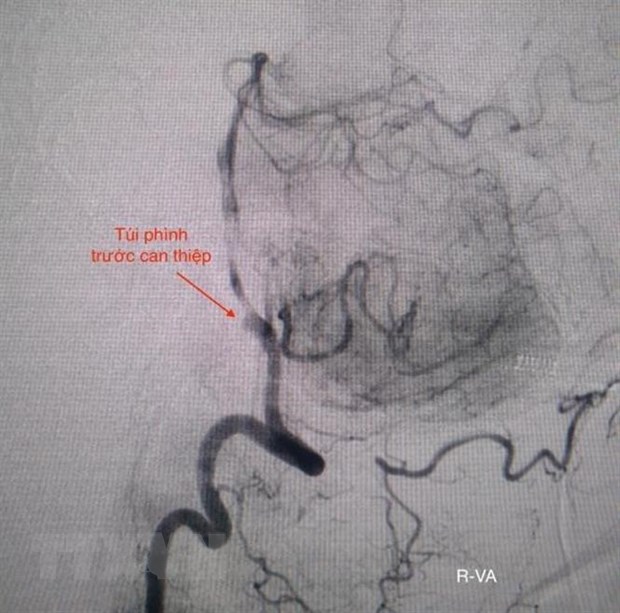

Hình ảnh túi phình động mạch trước can thiệp. (Ảnh: TTXVN phát)

Êkíp can thiệp nội mạch do bác sỹ Trịnh Thành Tín và cộng sự đã tiến hành đặt 3 coil (vòng xoắn kim loại) để bít túi phình.

Sau gần 2 giờ, các bác sỹ đã bít hoàn toàn túi phình mạch não và tái thông dòng máu trở lại bình thường. Bệnh nhân được chuyển đến Khoa Hồi sức tích cực-chống độc để hồi sức nội khoa sau can thiệp.